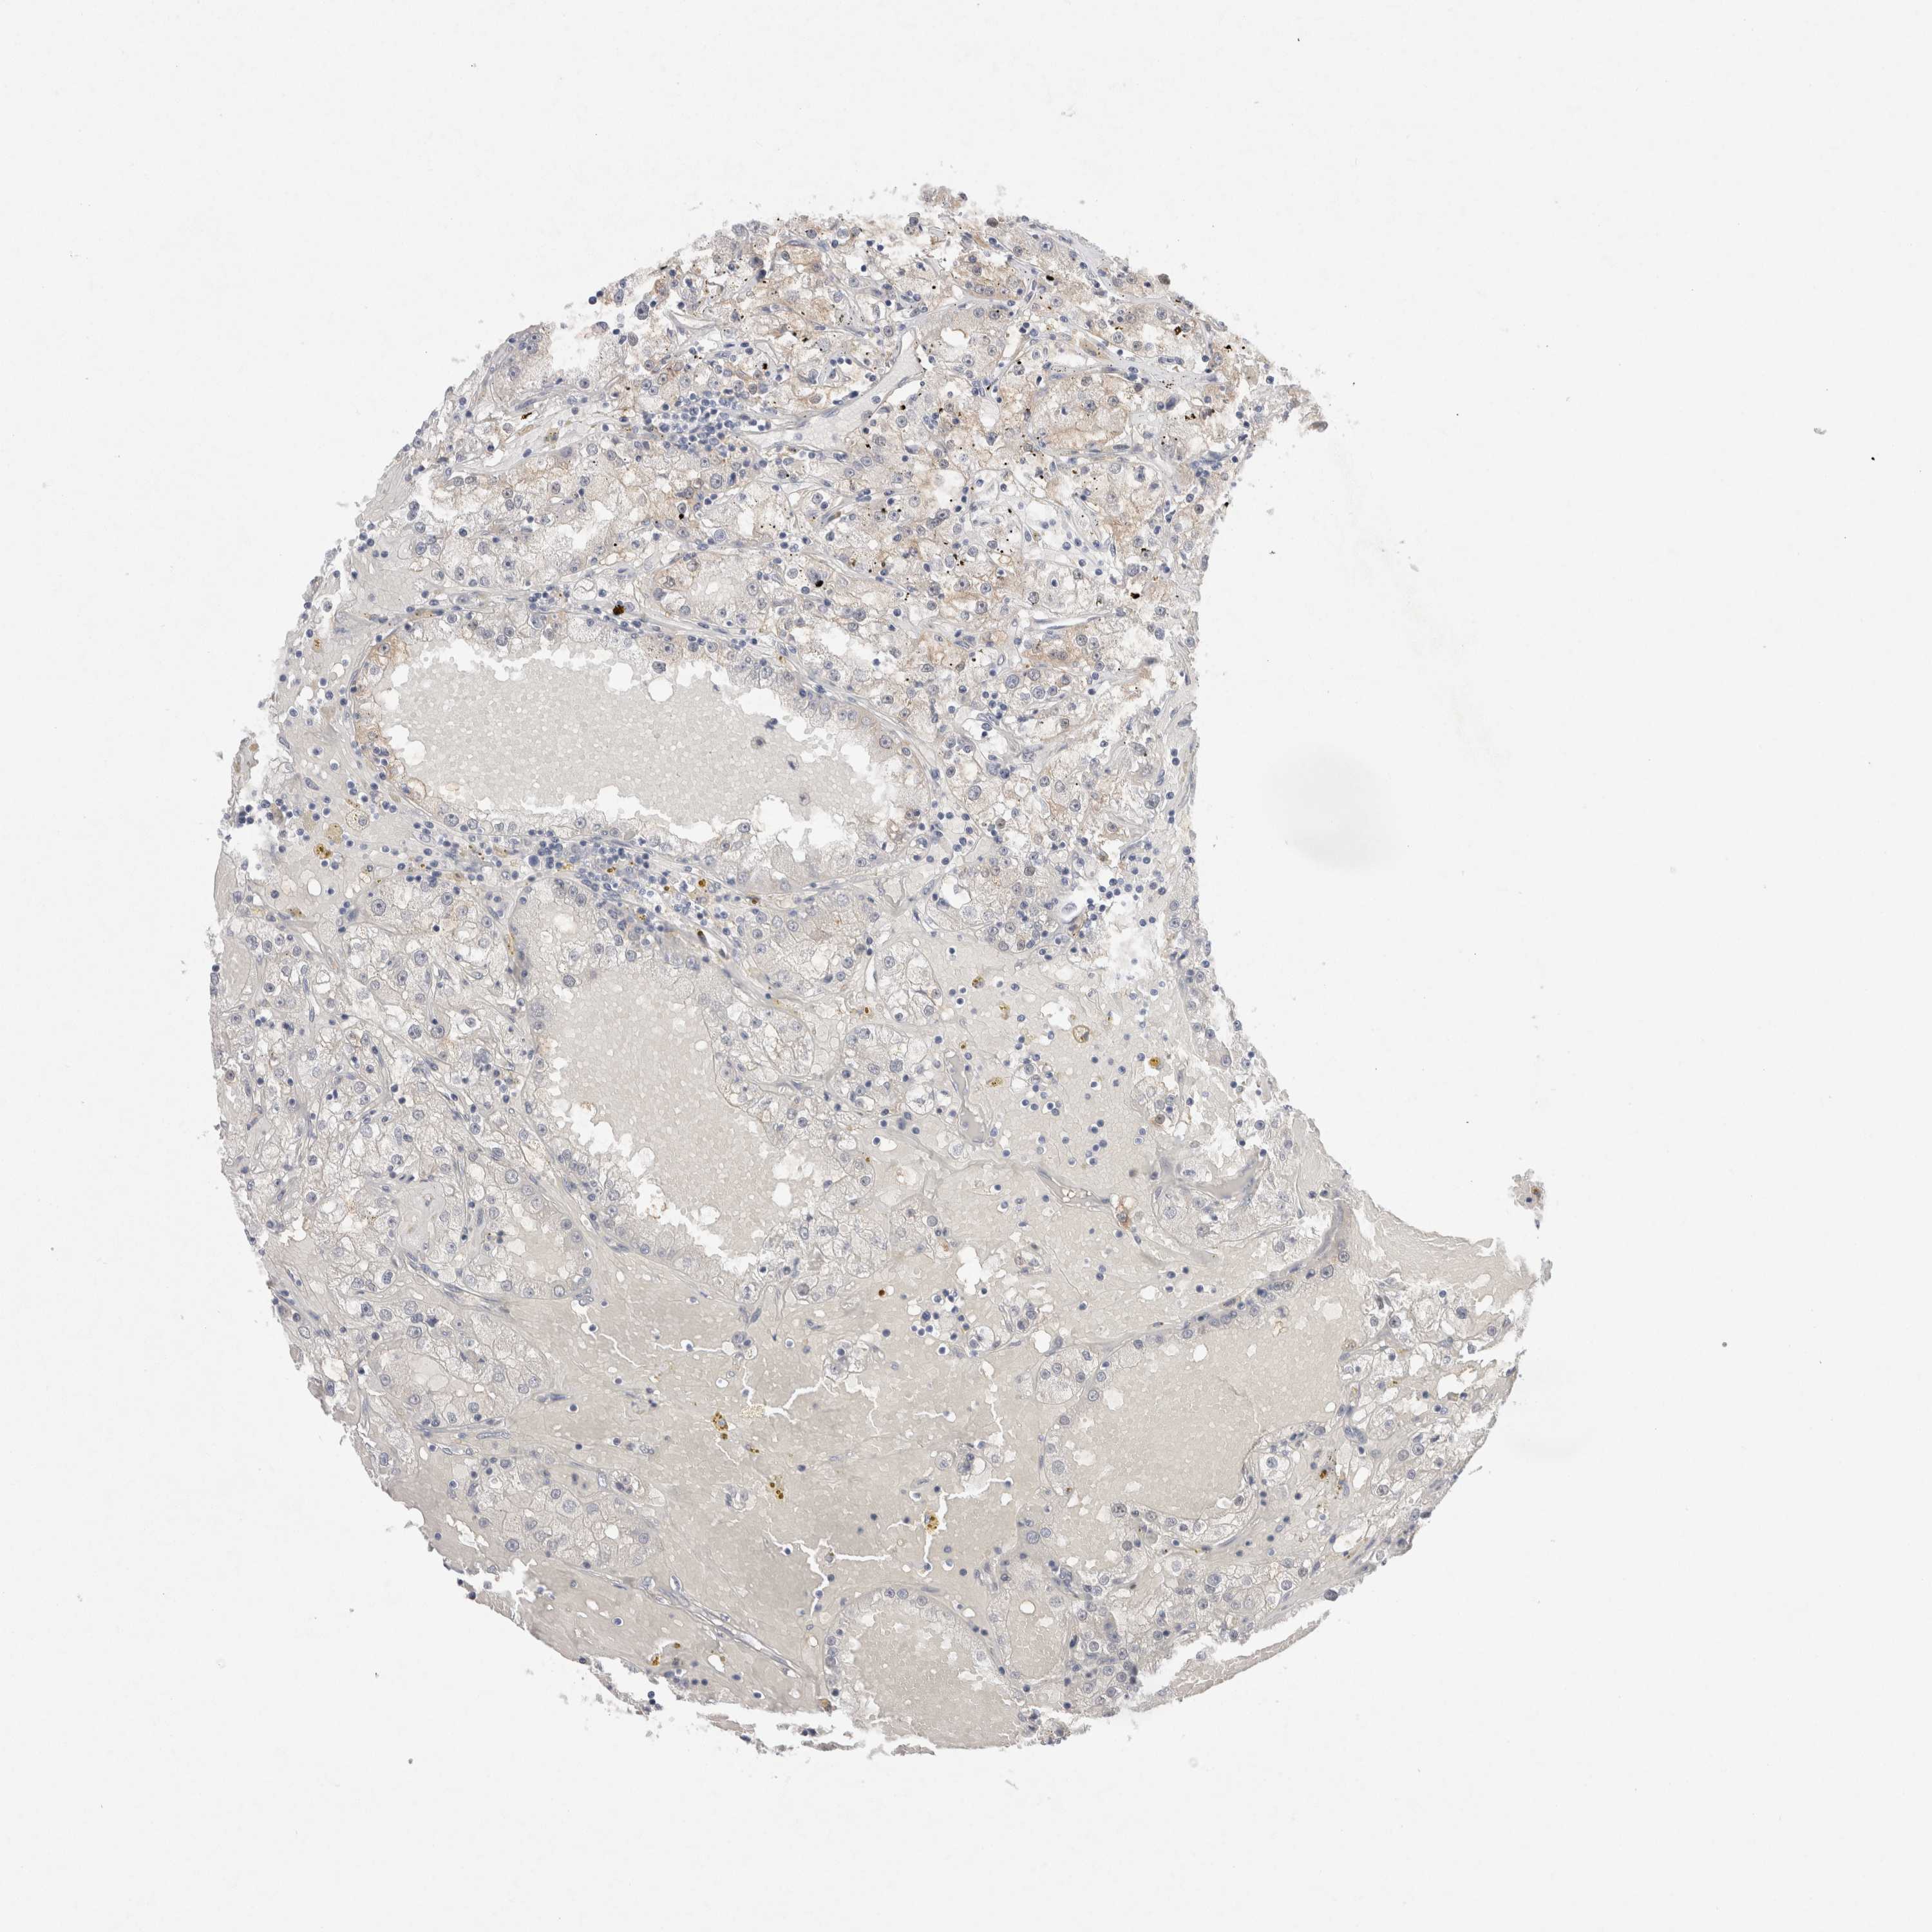

KIDNEY RENAL CLEAR CELL CARCINOMA (TCGA) - Interactive survival scatter ploti

The Survival Scatter plot shows the clinical status (i.e. dead or alive) for all individuals in the patient cohort, based on the same data that underlies the corresponding Kaplan-Meier plots. Patients that are alive at last time for follow-up are shown in blue and patients who have died during the study are shown in red.

The x-axis shows the expression levels (FPKM) of the investigated gene in the tumor tissue at the time of diagnosis. The y-axis shows the follow-up time after diagnosis (years). Both axes are complimented with kernel density curves demonstrating the data density over the axes. The top density plot shows the expression levels (FPKM) distribution among dead (red) and alive patients (blue). The right density plot shows the data density of the survived years of dead patients with high and low expression levels respectively, stratified using the cutoff indicated by the vertical dashed line through the Survival Scatter plot. This cutoff is automatically defined based on the FPKM cutoff that minimizes the p-score. The cutoff can be changed by dragging the vertical line or by entering a cutoff value in the square labeled "Current cut-off".

Under the Survival Scatter plot the p-score landscape (black curve; left axis) is shown together with dead median separation (red curve; right axis). Dead median separation is the difference in median mRNA expression between patients who have died with high and low expression, respectively. It is calculated as follows: median FPKM expression of dead patients with high expression - median FPKM expression of dead patients with low expression. This is intended to aid the user in visually exploring custom cutoffs and the associated p-scores and dead median separation.

Individual patient data is displayed and can be filtered by clicking on one or more of the category buttons on the top of the page. Categories describing expression level and patient information include: high, low, alive, dead, female, male and tumor stages. The scale of the x-axis can be toggled between linear and log-scale by clicking on the "x log" button. Mouse-over function shows TCGA ID, patient information and mRNA expression (FPKM) for each patient.

& Survival analysisi

Kaplan-Meier plots summarize results from analysis of correlation between mRNA expression level and patient survival. Patients were divided based on level of expression into one of the two groups "low" (under cut off) or "high" (over cut off). X-axis shows time for survival (years) and y-axis shows the probability of survival, where 1.0 corresponds to 100 percent.

WIPF2 is potential prognostic, high expression is favorable in Kidney Renal Clear Cell Carcinoma (TCGA)

Best expression cut offi

Based on the FPKM value of each gene, patients were classified into two groups and association between prognosis (survival) and gene expression (FPKM) was examined. The best expression cut-off refers the FPKM value that yields maximal difference with regard to survival between the two groups at the lowest log-rank P-value. Best expression cut-off was selected based on survival analysis .

When clicking on this number, the vertical dashed line indicating cut-off, the interactive survival plot, and the Kaplan-Meier curve will be adjusted to show results based on the best expression cut-off.

: 20.01

TCGA RNA samplesi

RNA-seq data is reported as average FPKM (number Fragments Per Kilobase of exon per Million reads), generated by the The Cancer Genome Atlas (TCGA) .

Normal distribution across the dataset is visualized with box plots, shown as median and 25th and 75th percentiles. Points are displayed as outliers if they are above or below 1.5 times the interquartile range. FPKM values of the individual samples are presented next to the box plot.

Average pTPM 17.0

Number of samples 521